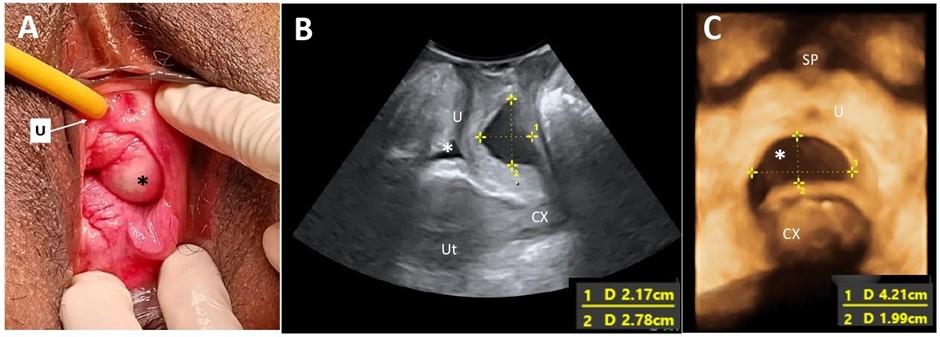

Cystic lesions of the vagina are relatively rare, and their prevalence may be underestimated due to underreporting of vaginal cysts. These lesions are classified according to their histological characteristics. A Gartner’s duct cyst, a benign variant, originates from the Gartner’s duct, which is a remnant of the mesonephric duct (Wolffian duct) in females. While these cysts are predominantly asymptomatic, they may be identified in patients presenting with pelvic organ prolapse. A comprehensive medical history, meticulous physical examination, and accurate imaging are essential for ensuring appropriate management of affected individuals.